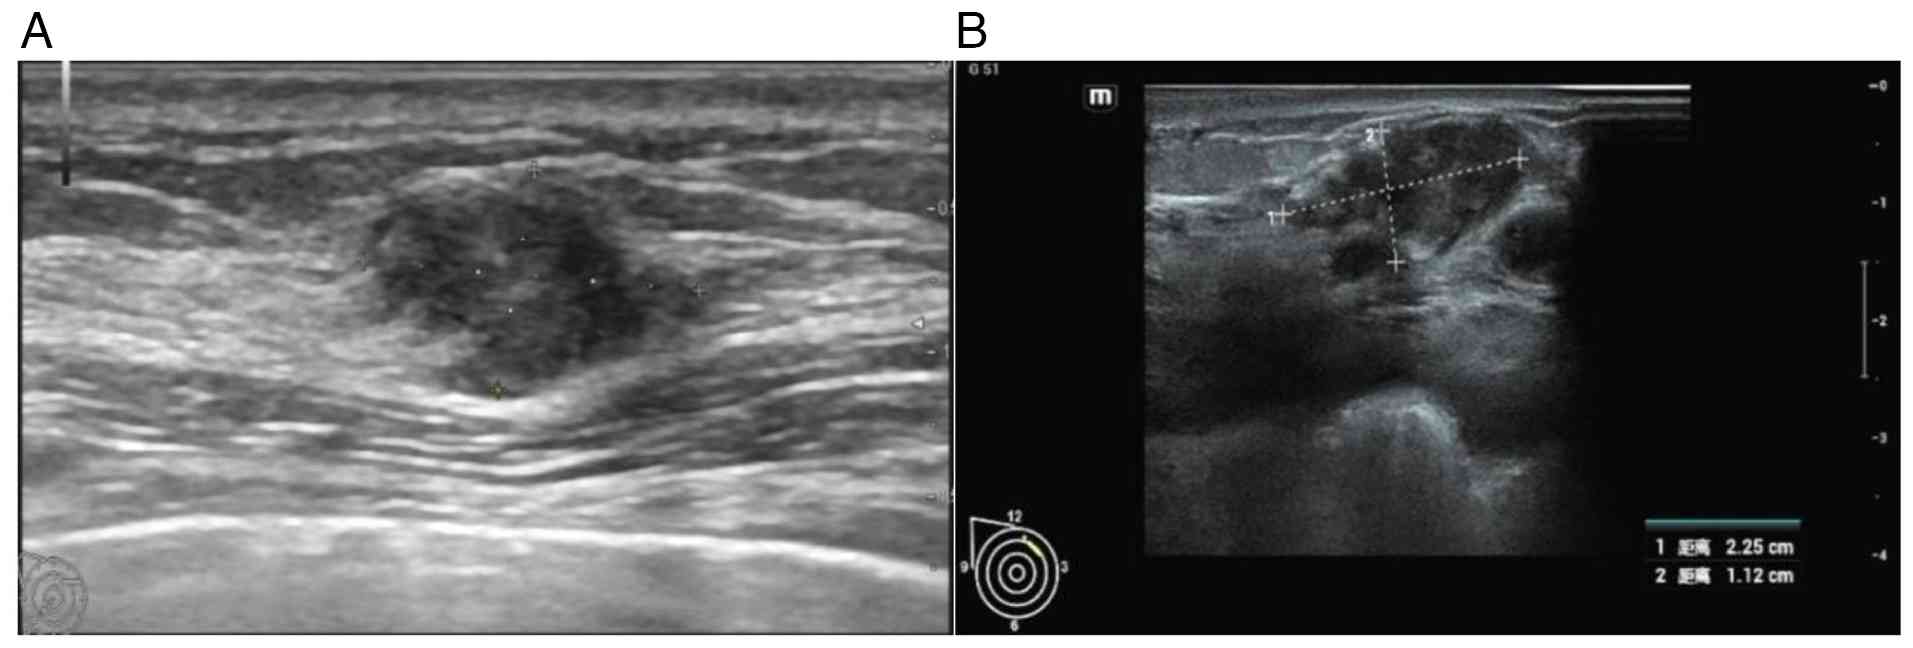

A right breast tumor was incidentally identified 1 month after a CT scan (June 2024). A color Doppler ultrasonography examination revealed a solid mass in the right breast, classified as Breast Imaging Reporting and Data System (BI-RADS) category 4A (Fig. 3A) (9). The right breast tumor was resected under local anesthesia. Based on postoperative pathology, immunohistochemistry (IHC) results and clinical history, the tumor was diagnosed as breast cancer secondary to a primary lung adenocarcinoma. An intravascular tumor thrombus was observed. IHC results (Data S1) demonstrated that the patient was positive for CK7, Ki-67 (~60% +), Napsin A and thyroid transcription factor 1 (TTF-1) and negative for estrogen receptor, progesterone receptor, CK5/6, Sox10, GATA binding protein 3, mammaglobin and HER2 (Fig. 4).

Color Doppler ultrasound results. (A)

June 2024 Breast color Doppler ultrasound: Hypoechoic area of right

breast, with unclear boundary and irregular shape. (B) August 2024

Breast color Doppler ultrasound: Blurred edge, irregular shape,

blood flow signals around.

Figure 3.

Color Doppler ultrasound results. (A) June 2024 Breast color Doppler ultrasound: Hypoechoic area of right breast, with unclear boundary and irregular shape. (B) August 2024 Breast color Doppler ultrasound: Blurred edge, irregular shape, blood flow signals around.

Asthma symptoms recurred 1 year after the first onset of illness (August 2024). Thin-layer CT and three-dimensional lung imaging (Fig. 1C) detected progressive atelectasis and a considerable right chest effusion. The right lung was not fully inflated and new inflammation was noted. Pleural fluid smears indicated cancer cells. Genetic analysis of the pleural effusion exhibited an EGFR exon 19 deletion and the exon 20 T790M missense mutation. The patient returned for a follow-up breast examination two months later, in August 2024. A breast color Doppler ultrasonography (August 2024) detected a solid mass of 2.25×1.12 cm in the upper quadrant of the right breast. The mass had blurred edges and was classified as BI-RADS category 5 (Fig. 3B). A physical examination indicated that the mass was hard and had poor mobility. After the patient's first diagnosis, follow-up was conducted every 2–3 months, with the last follow-up in February 2024. No other abnormalities were found during the follow-up. Therefore, based on the patient's medical history, recurrence of metastatic cancer after local resection is considered.